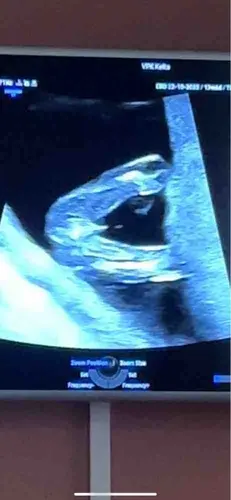

Kunnen jullie het geslacht raden馃檲 13 weken echo gehad

Een jongetje ?馃

Een jongen denk ik馃構